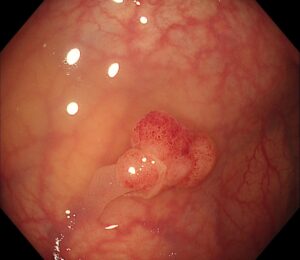

検査の結果、S状結腸に約12mmの有茎性ポリープ(Ip型) を発見しました🍄(写真1)

(写真1)